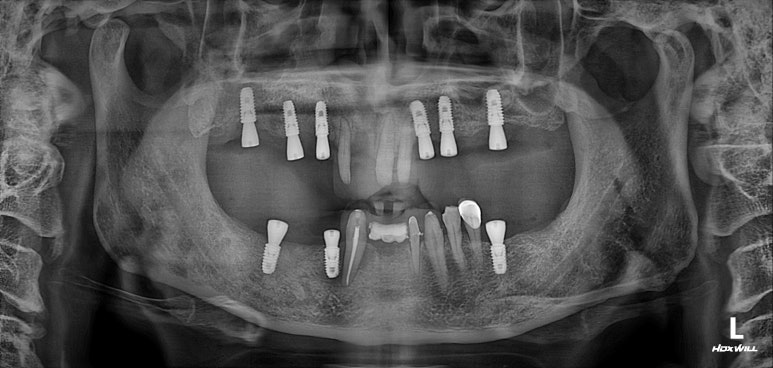

임플란트 2차수술을 하였습니다.

3개월이 지나면, 본인의 잇몸뼈와 임플란트가 단단한 골유착을 형성합니다.

비교적 씹어먹을 수 있게 임플란트가 고정이 되었다는 말씀 !!

잇몸안에 묻혀있는 임플란트를 나중에 머리와 연결할 수 있도록, 통로를 만들어주는 임플란트 2차수술을 시행합니다. 잘 보시면 뭔가 더 길어진 것처럼 보이실거에요~

전체 임플란트 완성!!

제가 개원하고 약 1년 뒤에 시작했던 케이스라 임상 사진이 많이 없네요...

임플란트 2차 수술을 하고나서, 구강스캐너를 이용하여 뽄을 뜨고나면- 맞춤형 지대주와 임시 크라운을 제작할 수 있게 되고 가장 먼저 할 일은 씹어보는 연습입니다.

보여드린 50대 남자 환자분처럼 어금니를 모두 재건해내는 경우, 씹는 행위에 대해 감이 많이 사라져있으시겠죠? 그래서 임시치아를 이용하여 씹는 연습을 해보셔야 한답니다.

어느 정도 적응이 되시면, 그 교합을 반영하여 최종 임플란트 크라운을 제작하게 되고 위와 같이 깔끔하게 완성되게 됩니다...